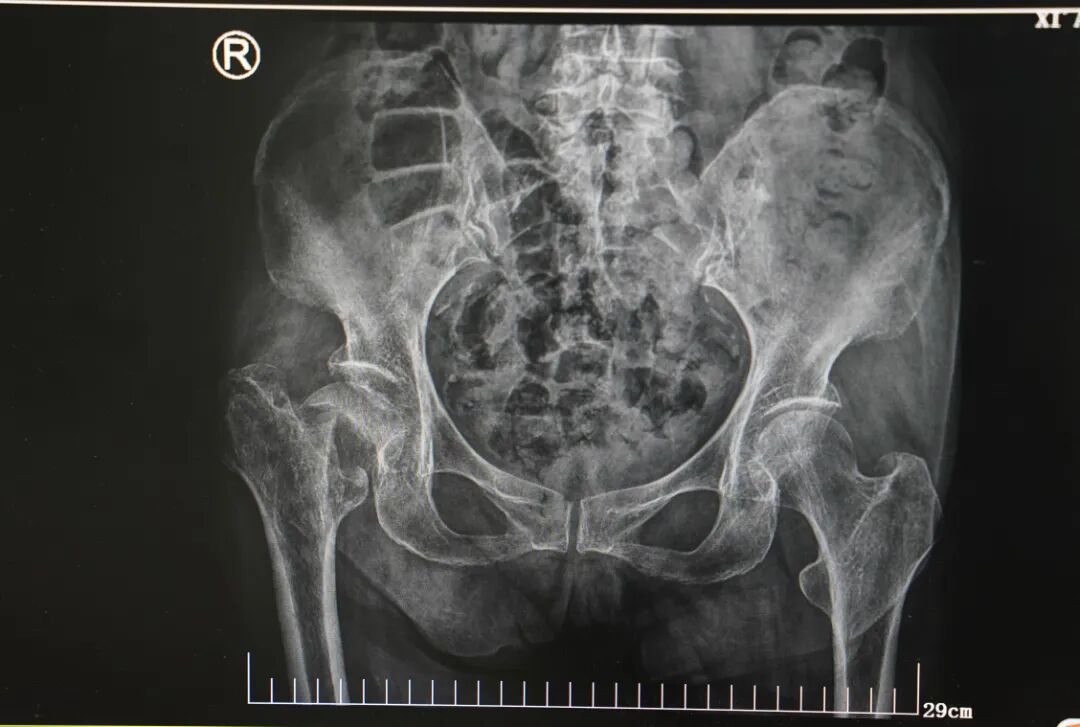

家人将她送到家附近的医院,CT 结果显示:髋部骨折。

然而,术前检查却发现了更棘手的问题——人的心脏有 3 根冠状动脉,而刘奶奶的 2 根冠状动脉都「堵」了,狭窄程度高达 95% 以上,属于冠心病的极高危病人。

3 根血管「堵」了 2 根

经综合评估,心脏病院执行院长李伟杰冒着巨大的风险,仅用一次手术开通 2 根闭塞的血管,置入 5 根支架,最大限度缩短了患者术后双抗治疗的时间,为后续骨科手术争取了宝贵窗口。

术中,麻醉手术二科副主任李思远为她保驾护航,闫天胜主任在何其濂副主任医师、张晖、张晓敏医生的协助下,为老人置换了右侧人工股骨头。